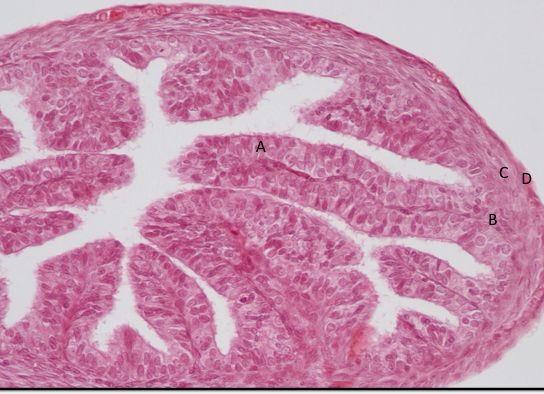

jajowód nr 412

od środka nabłonek jednowarstwowy walcowaty urzęsiony

blaszka właściwa

mięśniówka gładka

błona surowicza